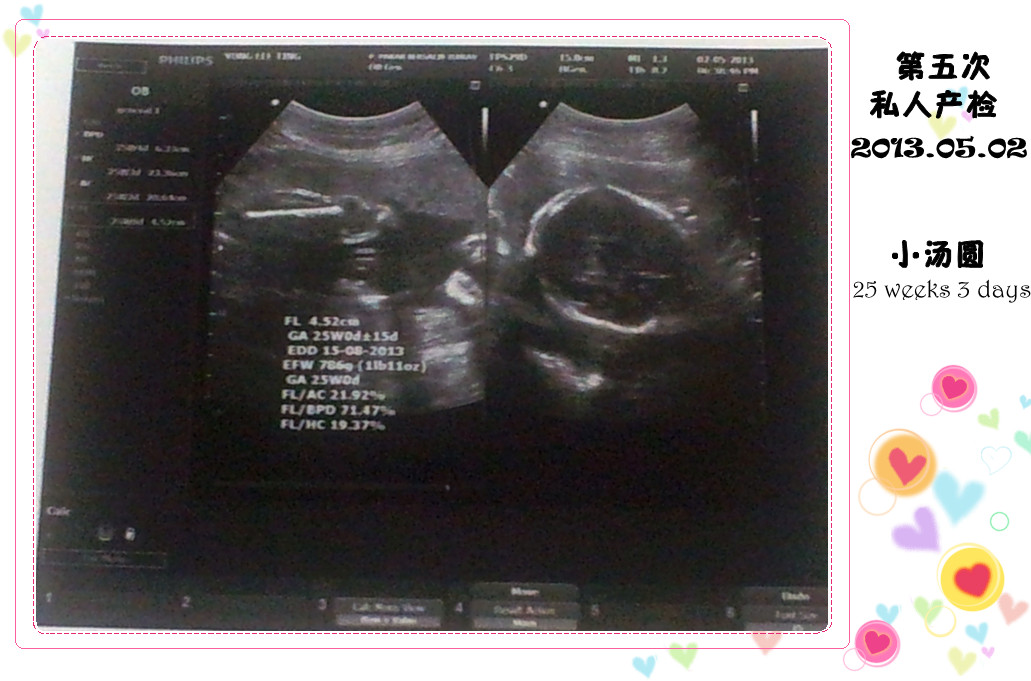

(๑•ᴗ•๑ )♡ 第五次私人产检 ♡(๑•ᴗ•๑ )

2013年05月02日,星期四

小汤圆: 25 weeks 3 days,786 gm

妈咪体重: 60 kg

小汤圆还是一样很合作啦

脚开得大大的

医生说性别是绝对不会错了啦

是个小蛇仔,呵呵

医生再扫描了小汤圆的头,腰,脸部等

都说小汤圆一切都发育的很好

都在标准之内

好玩的小汤圆还跟我们招手咧